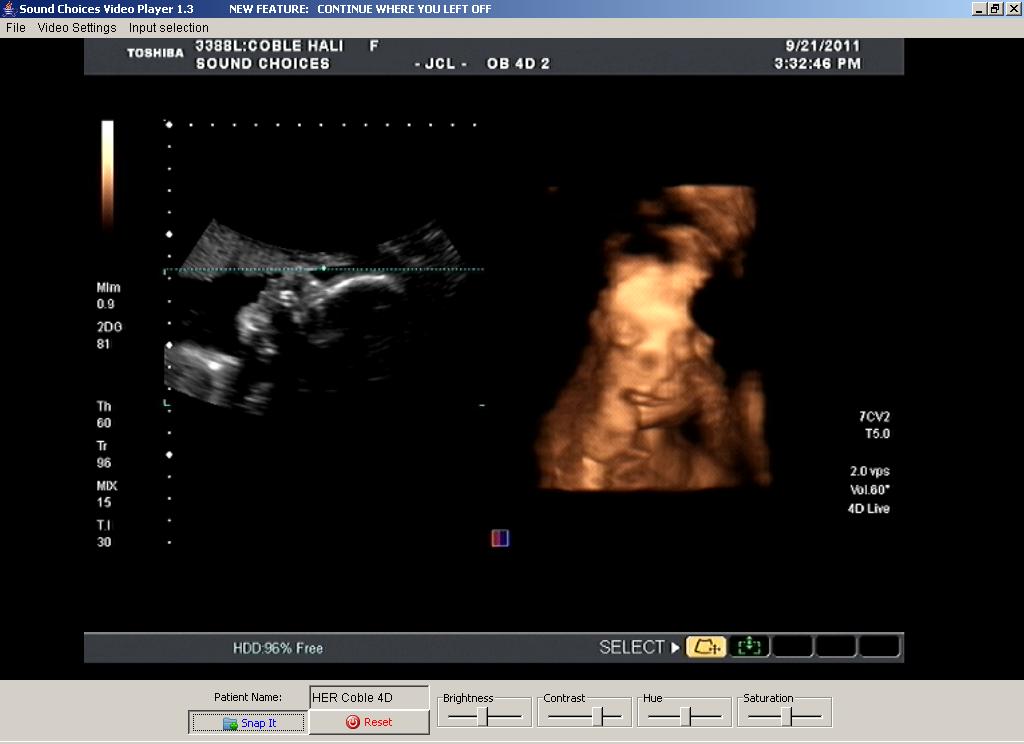

We've had quite a few ultrasounds (yea!) but Darin and I decided we wanted to do a 4D ultrasound just for the heck of it.  The following pictures are from September 21.

| Face...and a little smile? |